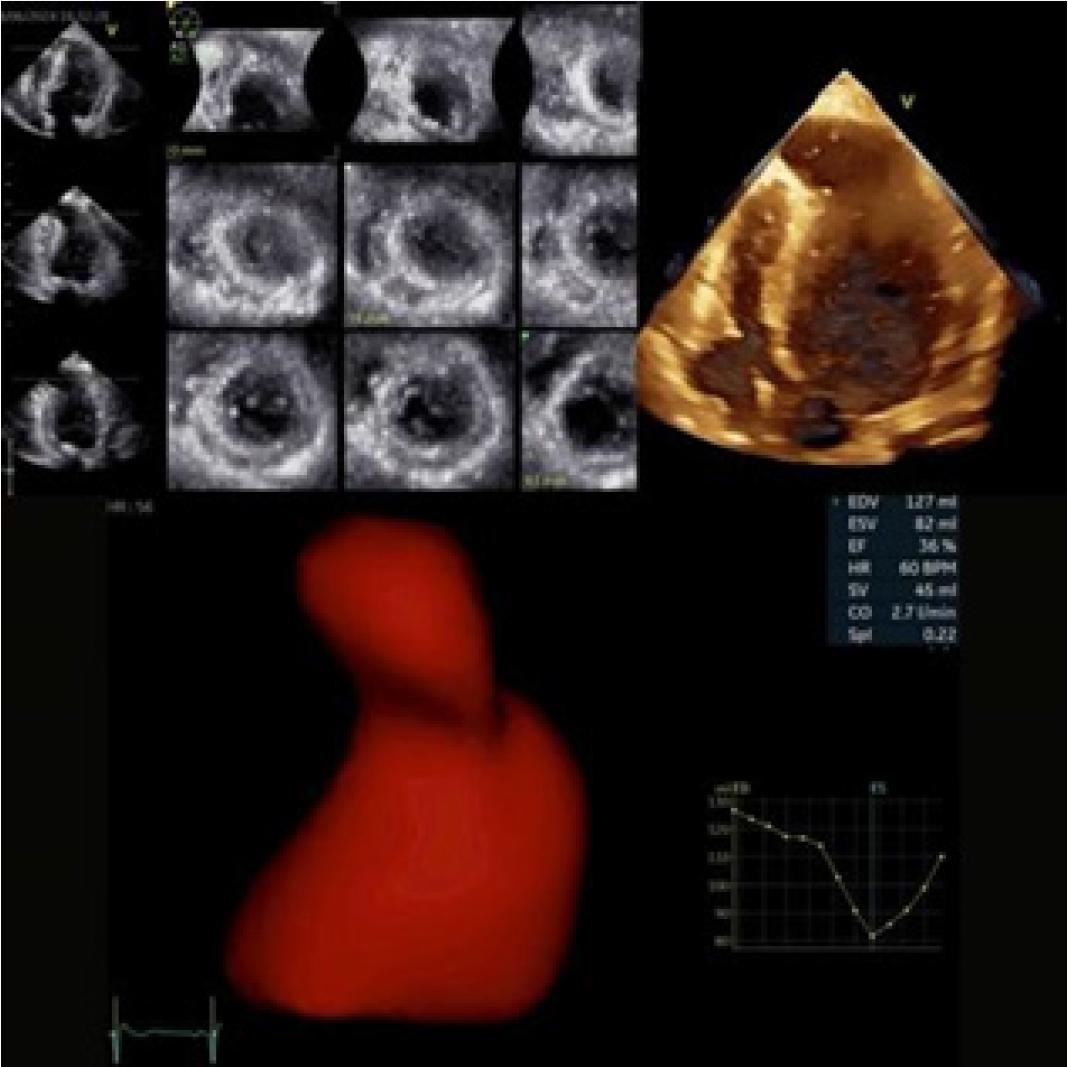

Figure 3